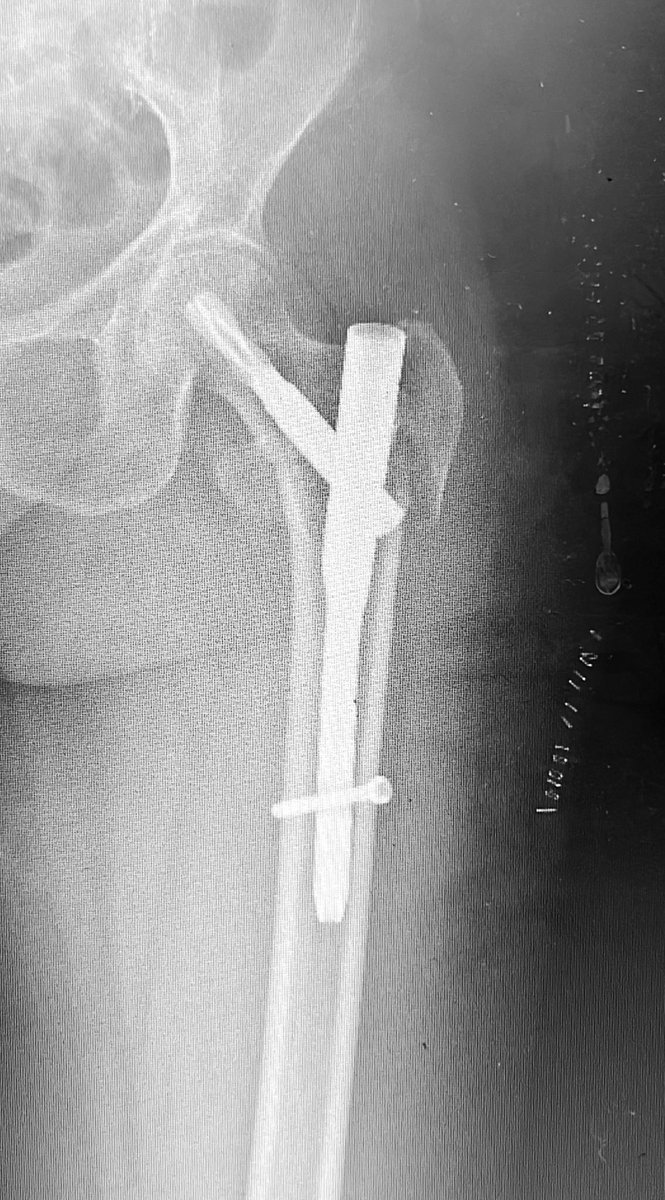

77 yo, pluripathological patient, combo nail and plate. Suprapatellar nail

Dr. Diego López tweet mediaDr. Diego López tweet mediaDr. Diego López tweet media